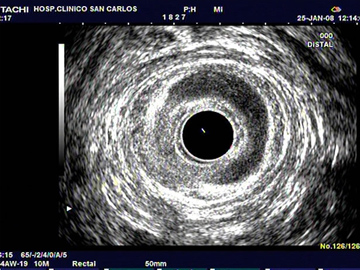

ECO Sonograma transanal